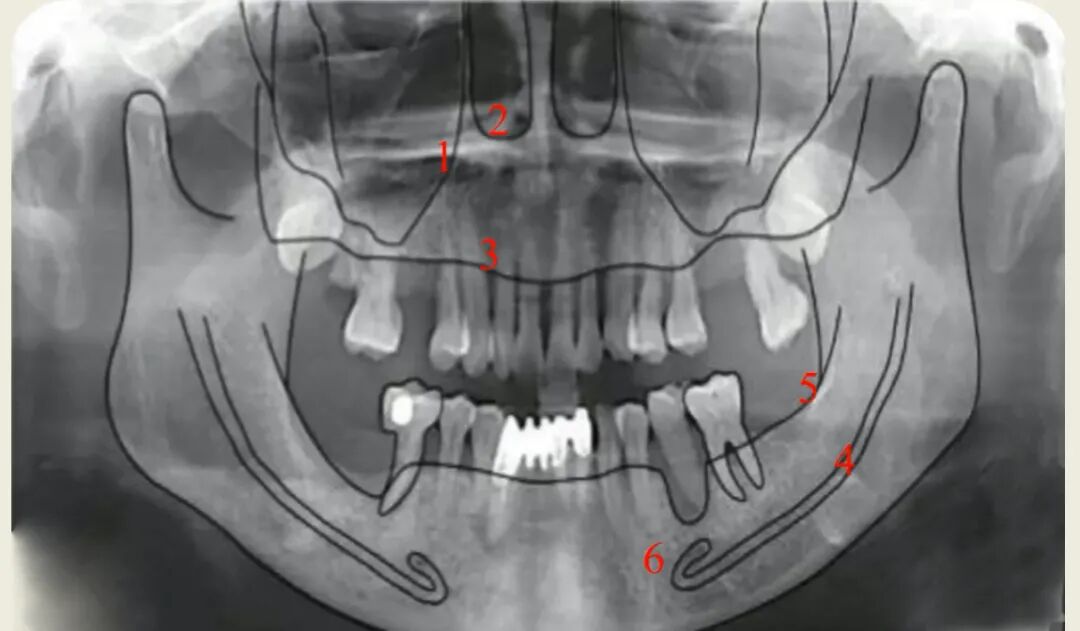

曲面断层片可看全貌但看不了横断面,例如前牙唇腭侧断面、后牙骨板厚度、后牙颊舌向断面,可能会造成备洞侧穿的后果,但可通过术前术后对比发现,还可以用骨形貌图弥补曲断的不足,通过描出关键结构测算骨高度。

曲面断层片怎么看种植术前读片,学会看CBCT、曲断片、根尖片_https://www.jmylbn.com_新闻资讯_第4张

骨形貌图

曲面断层片怎么看种植术前读片,学会看CBCT、曲断片、根尖片_https://www.jmylbn.com_新闻资讯_第5张

描片